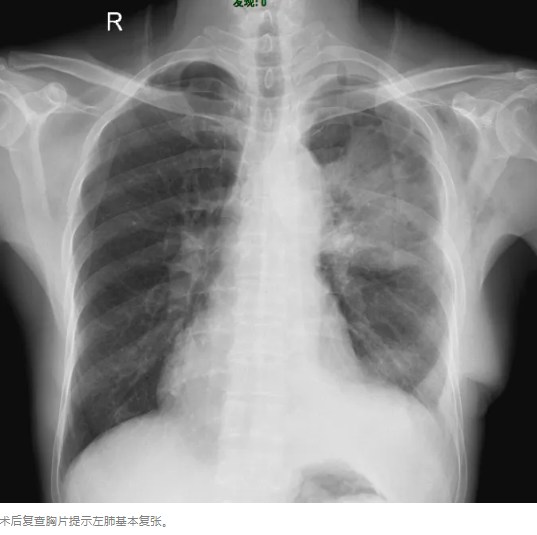

在术前各种准备完善后,2024年9月18日顺利行手术切除,术中出血少,无需输血。肿瘤大小约25cm*20cm*23cm,重2.6KG。术中胀肺,使患者肺获得完全复张。术中、术后患者病情稳定,无需转重症监护病房,返回普通病房进一步治疗。第二天,患者顺利下床活动,复查胸片提示恢复好。

1、患者左肺基本复张,明显缓解患者气促症状,提高术后生活治疗;